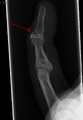

- X-ray showing fracture at the insertion of the extensor tendon